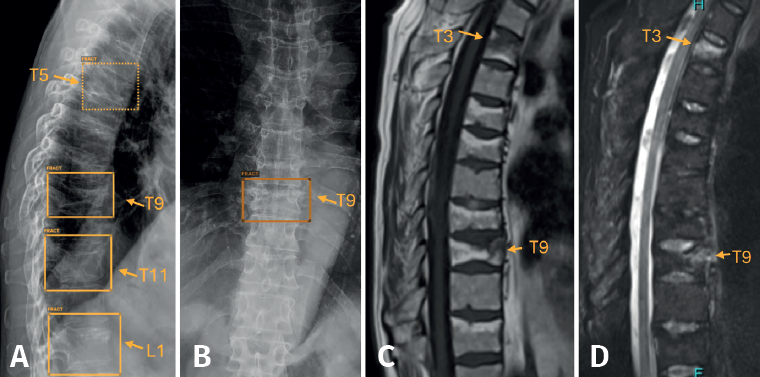

En nuestro caso, decidimos que toda radiografía que llega al PACS se enviara directamente y de manera automática al análisis por la IA, evitando un uso “a demanda” del médico, para favorecer su consulta. El resultado del análisis es devuelto al PACS en un plazo de 1-2 minutos, poniéndolo a disposición del personal médico para su valoración. Los resultados se presentan de manera clara y fácil de interpretar, en 3 niveles: negativo, dudoso o positivo (Figura 2); los dos últimos señalan con un recuadro en la radiografía la imagen de fractura. La diferencia entre un resultado positivo (recuadro con línea continua) y uno dudoso (recuadro con línea discontinua) estriba en un nivel de confianza alto o intermedio para la lesión detectada. Esta solución de IA detecta fracturas en todas las localizaciones anatómicas excepto el cráneo y la columna cervical, y, además, identifica derrames articulares, luxaciones y lesiones óseas. Como control de calidad, se indica el número de imágenes recibidas y el número de imágenes analizadas.

Es importante entender que la IA señala las fracturas antiguas como “fractura”. En el caso de las fracturas aplastamientos vertebrales, la IA detecta los aplastamientos, pero únicamente una RM puede establecer si el aplastamiento es reciente, al identificar el edema óseo asociado (Figura 7).